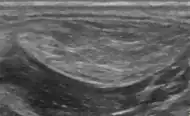

Medical ultrasonography of a lipoma in the thenar eminence: It is hyperechoic compared to adjacent muscle, and relatively well-defined, with miniature hyperechoic lines.[23] -